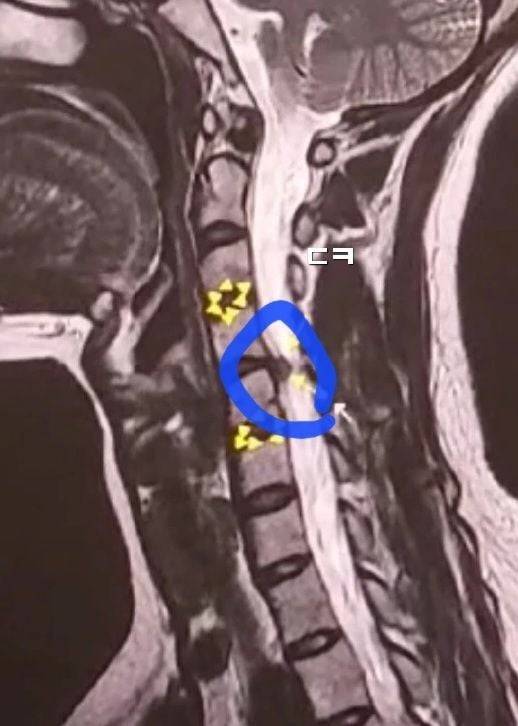

(내 mri. 터져나온 디스크가 신경을 반 이상 누르는 중)

난 c5=경추5번 터짐, 사진의 c5번 부위에 운동 마비 증상와서 팔에 힘 빠짐 + 떨림. 프라이팬도 못들게 됨. 팔 들려고하면 5초이상걸림 팔이 억지로 서서히...느리게 올라감.